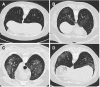

Hermansky-Pudlak syndrome (HPS) is a rare autosomal recessive genetic disorder characterized by oculocutaneous albinism and a bleeding diathesis due to platelet dysfunction. More than 50% of cases worldwide are diagnosed on the Caribbean island of Puerto Rico. Genetic testing plays a growing role in diagnosis; however, not all patients with HPS have identified genetic mutations. In Puerto Rico, patients with HPS are often identified shortly after birth by their albinism, although the degree of hypopigmentation is highly variable. Ten subtypes have been described. Patients with HPS-1, HPS-2, and HPS-4 tend to develop pulmonary fibrosis in Puerto Rico; 100% of patients with HPS-1 develop HPS-PF. HPS-PF and idiopathic pulmonary fibrosis are considered similar entities (albeit with distinct causes) because both can show similar histological disease patterns. However, in contrast to idiopathic pulmonary fibrosis, HPS-PF manifests much earlier, often at 30-40 years of age. The progression of HPS-PF is characterized by the development of dyspnea and increasingly debilitating hypoxemia. No therapeutic interventions are currently approved by the U.S. Food and Drug Administration for the treatment of HPS and HPS-PF. However, the approval of two new antifibrotic drugs, pirfenidone and nintedanib, has prompted new interest in identifying drugs capable of reversing or halting the progression of HPS-PF. Thus, lung transplantation remains the only potentially life-prolonging treatment. At present, two clinical trials are recruiting patients with HPS-PF to identify biomarkers for disease progression. Advances in the diagnosis and management of these patients will require the establishment of multidisciplinary centers of excellence staffed by experts in this disease.